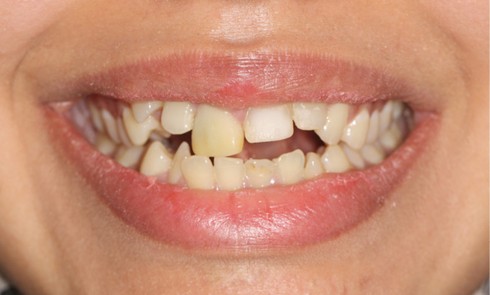

Article réservé à nos abonnés Quand l’orthodontie se fait réparatrice

Diagnostic Le niveau d’hygiène est alarmant, car le rituel du brossage des dents n’est pas instauré dans la famille. Des...